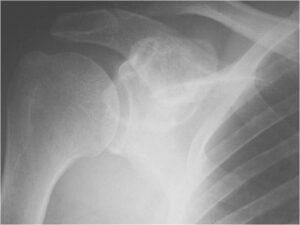

Radiographic Presentation

Radiology emulates pathology: Biphasic Tumor

- One region low grade chondrosarcoma

- Second more aggressive area with bone destruction, lysis of calcification, soft tissue mass

- Cortical permeation and a soft tissue mass in 70% of cases

Ill-defined, lytic intraosseous lesion

- Or extraosseous soft tissue mass

- Devoid of calcifications in continuity with lesions having the features of a cartilaginous tumor

Characteristically abrupt transition between chondroid tumor and dedifferentiated, lytic component

Bone may be expanded and adjacent cortex thickened